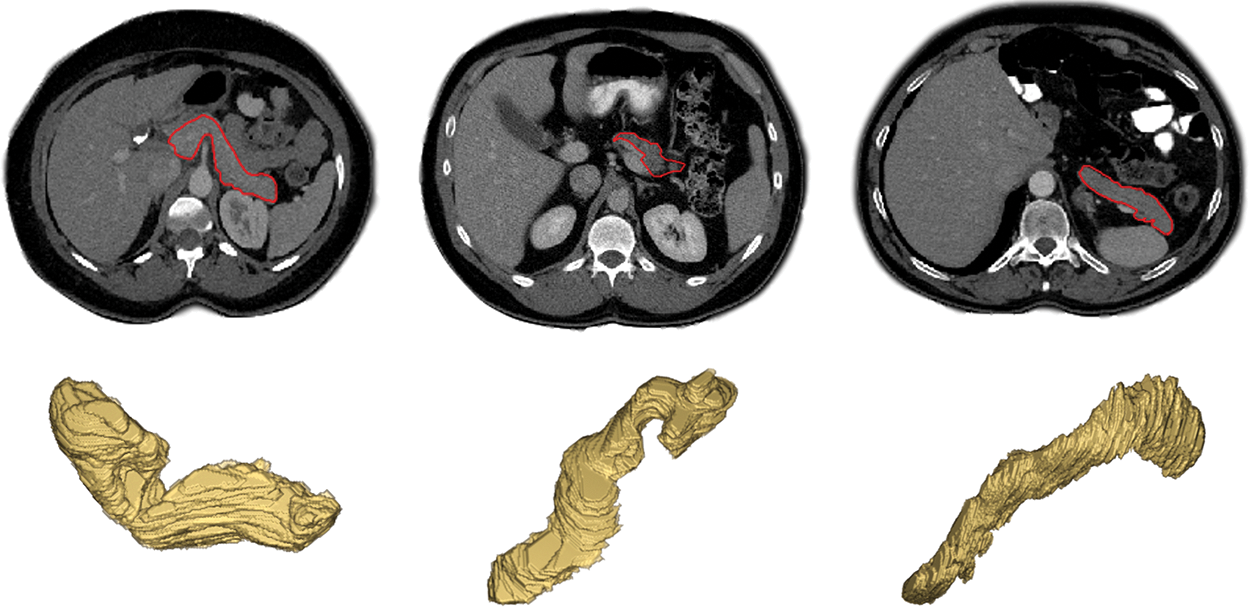

According to national cancer registry center (cancer hospital chinese academy of medical sciences) data released in 2022 [1], pancreatic cancer is a malignant tumor with a 5-year survival rate of 5 percent. Fortunately, early diagnosis and treatment can improve the prognosis of pancreatic cancer, then preventing its further deterioration. Accurate pancreas segmentation can help us reduce the impact of the other organs on the detection of tumor areas earlier and make it easier to treat it in advance to improve survival [2]. In addition, the segmented pancreas can be used for volumetric measurements, 3D reconstruction, and visualization, which can greatly benefit the pancreatic diseases diagnosis [3]. Meanwhile, compared to the segmentation of abdominal liver, spleen and kidney, the segmentation accuracy of pancreas is the lowest at present because of the following three reasons: (1) the small size of pancreas in abdominal image, (2) the blurred boundary between pancreas and its surrounding tissues, and (3) the high variabilities in shape, size and location between inter and intra slices, as shown in Fig. 1 [4]. Hence, the research of pancreas segmentation is extraordinary essential, and it is of great significance to improve the accuracy of pancreas segmentation.

Figure 1: Examples of variations in appearance, shape, size and location of the pancreas as seen on contrast enhanced CT after removal of the image background by masking the patient’s body